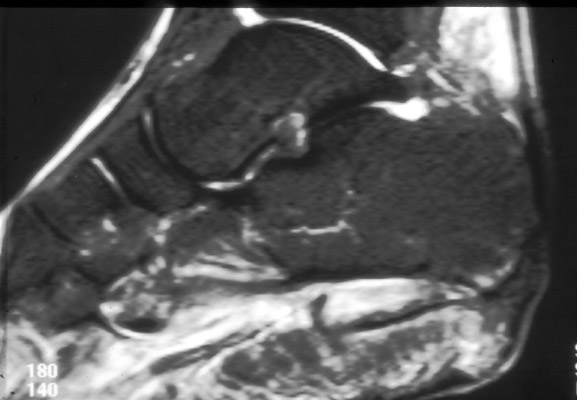

Gout

images/LARGE/72goutMRcor.JPG

images/LARGE/71goutMRsag.JPG

images/LARGE/73goutMRaxt2.JPG

images/LARGE/74goutMRaxpd.JPG